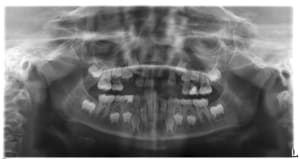

06112015_185219_cj8opl.jpg